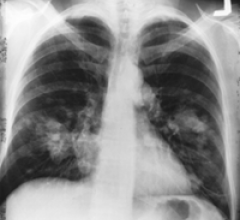

August 11, 2011 -- The New England Journal of Medicine's recent publication of the landmark National Lung Screening Trial (NLST), along with two congressional initiatives and an industry report, herald a much brighter future for lung cancer patients.